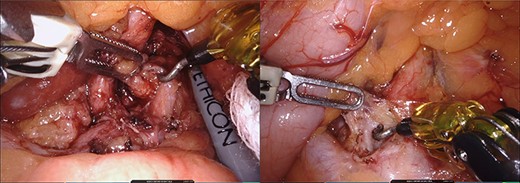

Initially, the left lateral segment of the liver was retracted and the gastro-hepatic ligament was divided to facilitate the identification of the right crus of the diaphragm. The local anatomy made difficult to access the celiac trunk through the gastro-hepatic ligament. The lesser sac was approached opening the gastro-colic ligament, and lifting up the posterior wall of the stomach using the robotic third arm. This maneuver also put in tension the left gastric artery making easier to reach the celiac trunk. All associated lymph nodes and fibrotic tissue that were crossing in front of the origin of the common hepatic and splenic artery were removed (Fig. 3). The dissection continued along the common trunk (Fig. 4). Neural fibers were divided and the origin of the celiac artery was fully exposed free (Fig. 5). Postoperative course was uneventful and the patient was discharged the next day without any dietary restriction. The pain was managed with acetaminophen only after discharge. At 5 months follow up, the patient showed complete resolution of symptoms.

Intraoperative images during lymphanedectomy. Legend: left: lymphadenectomy on the left side of the celiac trunk. Right: lymphadenectomy on the right side of the celiac trunk.